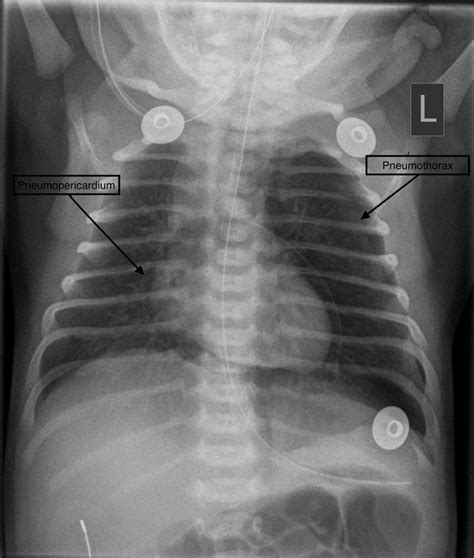

• Chest X-ray: This is the primary diagnostic tool for pneumothorax. A chest X-ray can show the presence of air in the pleural space and the extent of the lung collapse.